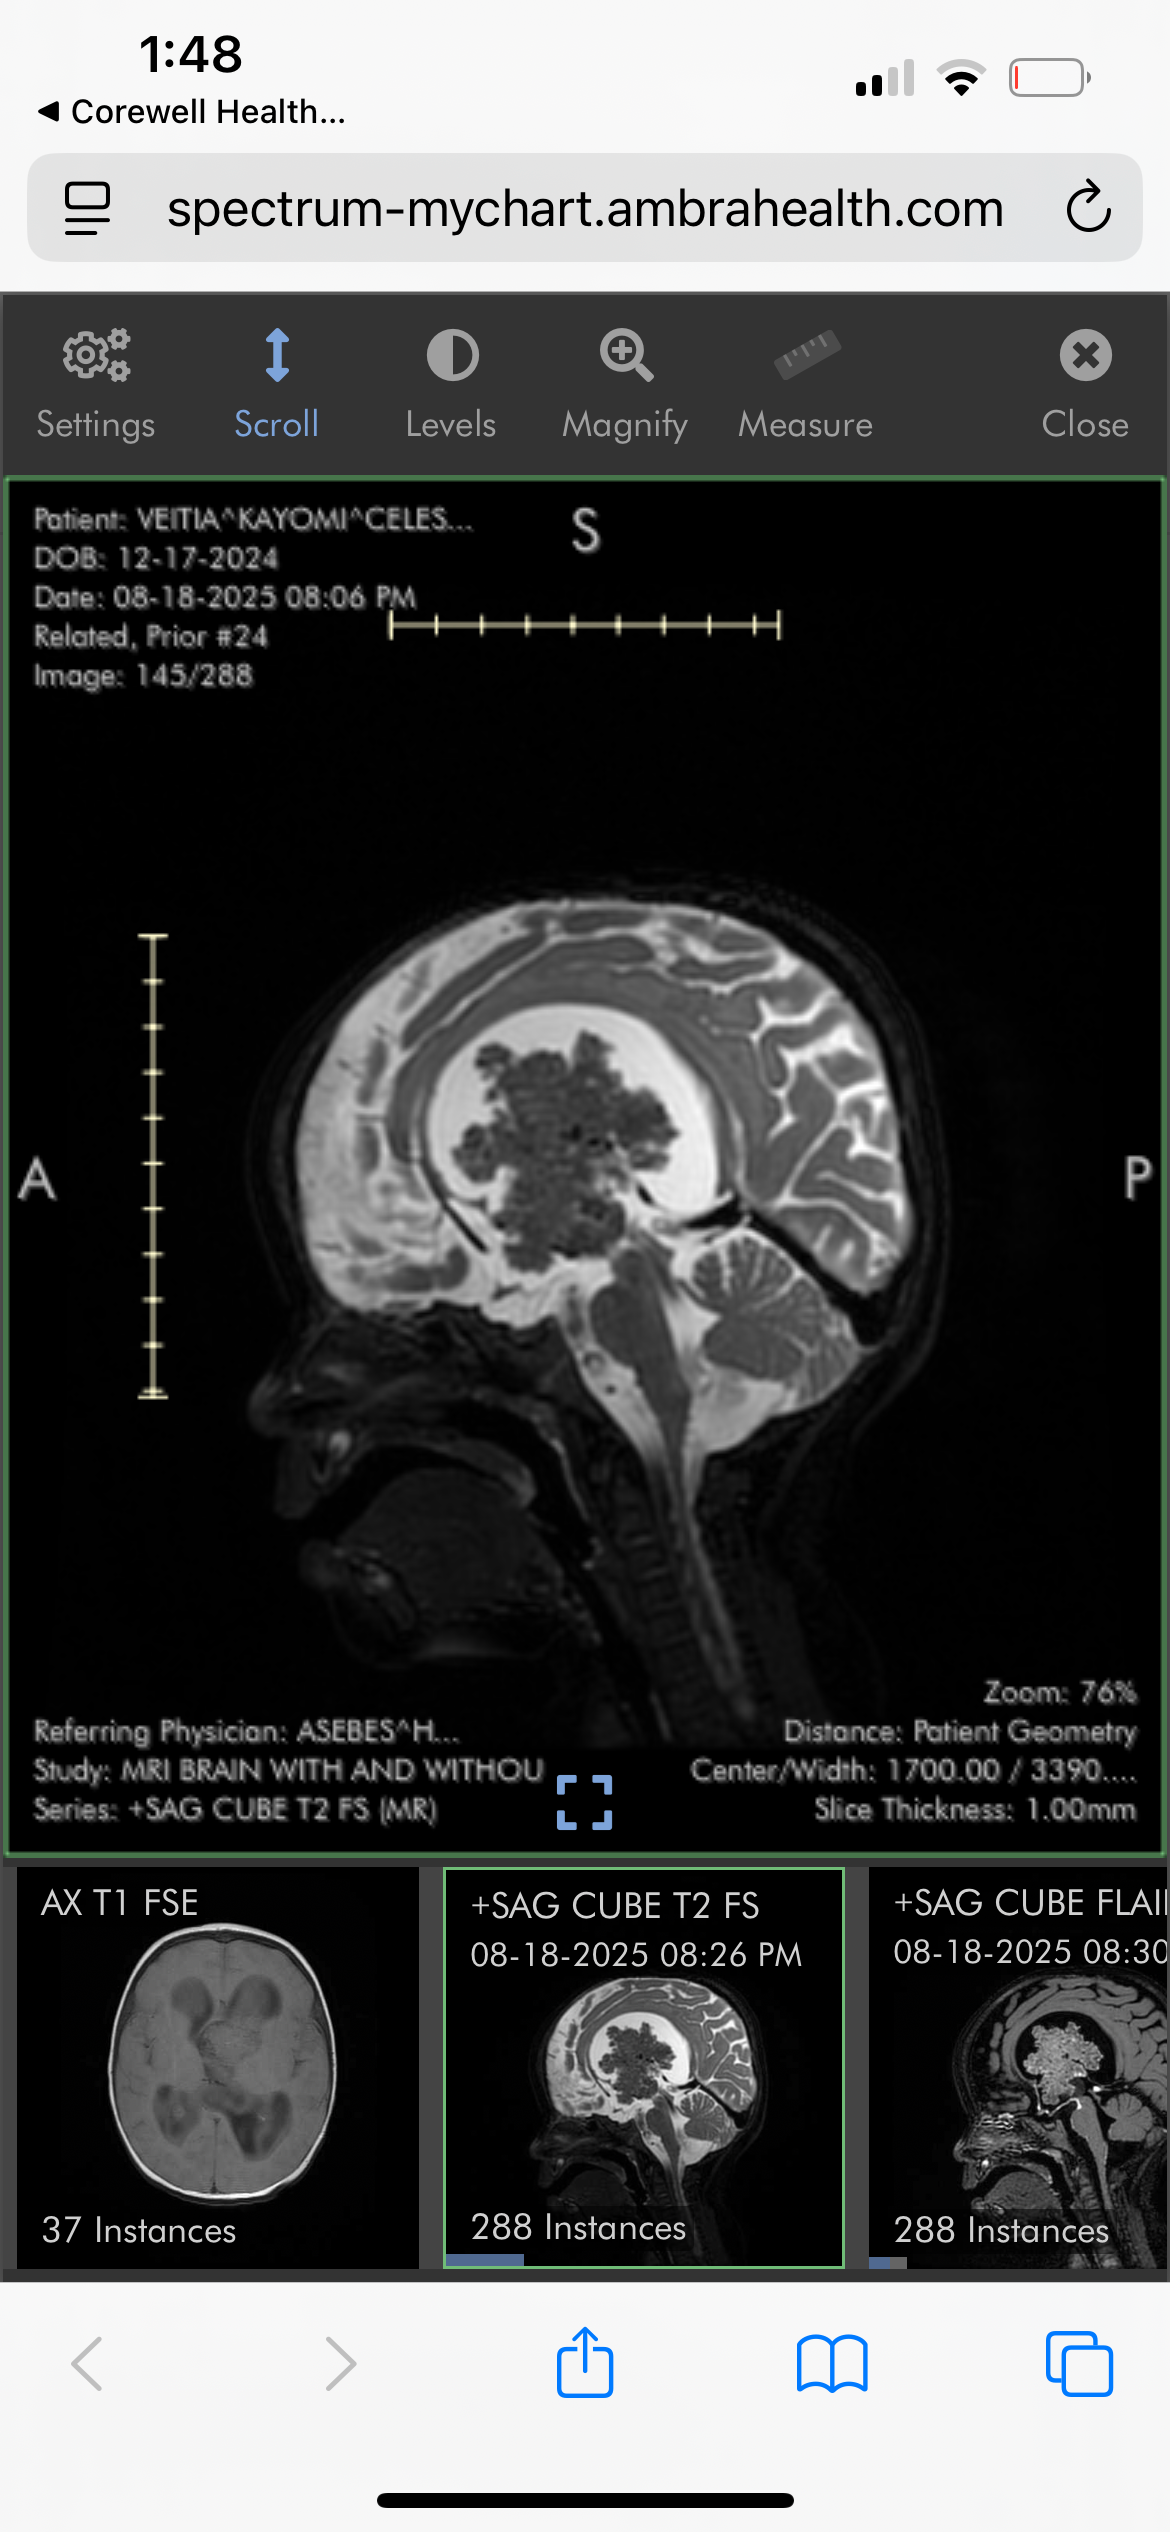

My name is Taylor, I am 20 years old and the mother of 10-month-old Kay’Omi Celeste. On August 18th, 2025, my then 8-month-old, Kay’Omi, was unexpectedly diagnosed with a large brain tumor.

This has changed both of our lives drastically overnight. Kay’Omi has had multiple surgeries within these two months. She has also had multiple doctor’s appointments and long hospital stays. We are currently unsure if the tumor is cancerous or not, or what exactly it is, but she is getting chemotherapy just in case it is and to shrink it before they are able to take it out. I’m still processing the fact that my baby is going through this so young.